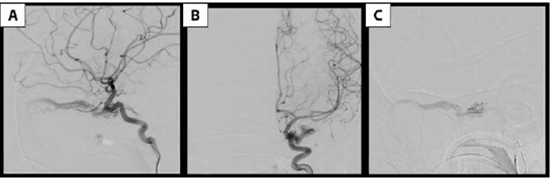

La arteriografía evidencia fístula carótido-cavernosa indirecta izquierda tipo D de la clasificación de Barrow. Presenta aferencias provenientes de la arteria carótida interna izquierda a través de un fino ramo corto carótido hipofisario, y de carótida externa izquierda a través de finos ramos de la arteria maxilar interna. El drenaje se produce hacia una vena oftálmica superior dilatada con flujo lento y hacia los senos petrosos (Figura 2yFigura 3).

Figura 2:Angiografía digital que muestra FCC indirecta izquierda tipo D de la clasificación de Barrow, alimentada por la arteria carótida interna izquierda a través un fino ramo corto carótido hipofisario. Seevidencia el drenaje hacia el seno cavernoso y de ahí a una dilatada vena oftálmica superior. A)Inyección por carótida interna izquierda, proyección lateral. B) Inyección por carótida interna izquierda, proyección frente. C) Inyección supraselectiva con microcateter desde el fino ramo carótido hipofisario.